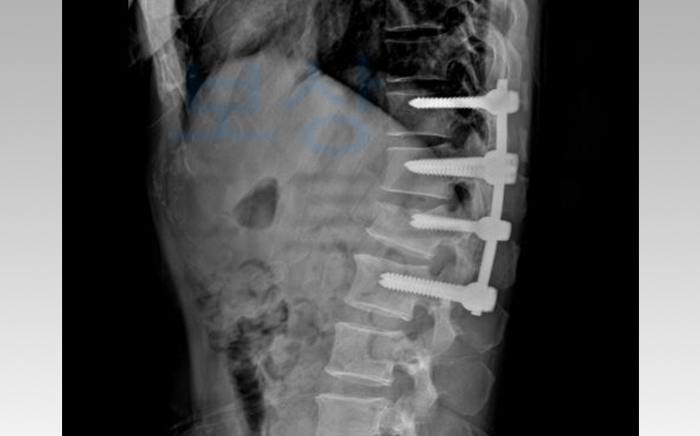

위 사진처럼 척추체 4개를 연결하는 척추 유합술을 시행하게 되셨는데요. 이후에는 몇 달간 척추 보조기 착용하여 요양하는 치료를 받으셨습니다. K 님께서는 보험금 처리를 위해서 먼저 상대방 가해차량으로부터 교통사고 합의금을 받으셔야 했는데요.